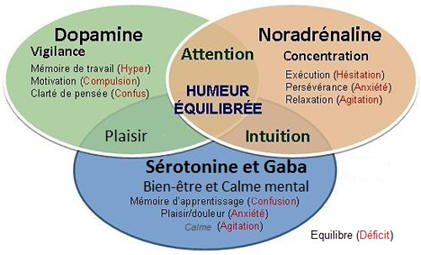

► C’est un déterminisme génétique (donc héréditaire), qui entraine, du point de vue neurologique, une mauvaise régulation de deux neurotransmetteurs principalement (excès ou carence) , la Dopamine et la Noradrénaline, notamment au niveau du lobe frontal et spécialement sa partie derrière le front, le cortex préfrontal (schéma ci-contre). – La Dopamine sert à réguler les circuits de la récompense, du plaisir, de l’énergie, de l’attention, de la vigilance et de la motivation. – Leur présence irrégulière dans les connexions entre les neurones au niveau de l’axone (schéma ci-dessus) entraine une inconsistance de l’attention, du plaisir et de la motivation, notamment pour les tâches ou les relations de la vie de tous les jours. ► Le cortex frontal sert à programmer, planifier, inhiber des comportements impulsifs, mais aussi avoir une bonne flexibilité mentale. Il doit en effet être capable de s’interrompre si quelque chose de prioritaire survient en pleine action. — Pour être attentif, on a besoin d’une bonne transmission de la dopamine dans ce cortex frontal, ce qui n’est pas souvent le cas avec le TDAH. – Cela se traduit de manière différente selon que l’on est dans une phase hyperactive ou hypoactive : – Si je suis hypoactif, c’est-à-dire avec peu d’énergie, je pense à une chose à faire qui me fait penser à autre chose, puis d’autres pensées arrivent encore. – Un haut potentiel associé à une des 8 formes formes d’intelligences recensées (mathématique, verbale, musicale, corporelle, visuelle, interpersonnelle, intrapersonnelle), peut construire une arborescence d’idées créative. – Mais souvent au final je n’ai rien fait, car je suis resté dans ma tête, et, de plus, je n’ai souvent rien mémorisé, car ce sont des pensées furtives non propices à la mémoire de travail. – Si je suis hyperactif, je commence une tâche, je l’interromps pour commencer autre chose puis autre chose sans lien avec la tâche prioritaire initialement commencée (hyperactifs). – j’ai fait une multitude de tâches ou j’ai parlé abondement, la plupart du temps sans intérêt par rapport à mes priorités et aux attentes des autres personne. ► Du point de vue neurologique, les fonctions exécutives sont regroupées en 6 familles (avec l’acronyme : A.F.F.A.M.É.E) : – ACTIVATION : s’organiser, structurer, synthétiser, prioriser, décider, initier la tâche en gérant le temps – FOCUS : maintien de l’effort et de la vitesse d’exécution, ou basculement vers une tâche prioritaire – ACTION : autorégulation des actions, ralentir, s’activer ou s’adapter selon les situations/personnes – MÉMOIRE : capacité à conserver et rappeler l’information en mémoire durant une tâche/conversation – ÉMOTIONS : savoir moduler l’émotion pour ne pas s’emporter facilement, savoir gérer la frustration – EFFORT : ne pas perdre l’intérêt dans la tâche et faire face aux difficultés dans un temps donné  ► Chacune de ces 6 familles de fonctions exécutives peut poser un problème si on a un TDAH. On parle aussi de syndrome dysexécutif. ⇒ Chacun peut faire son propre bilan neuropsychologique chez un neurologue moyennant finance, mais on peut résumer ci-dessous les principaux problèmes que rencontre la majorité des enfants et adultes TDAH : – Problèmes d’attention focalisée (concentration) et divisée (suivre plusieurs informations en simultané) – Problèmes de gestion des informations stockées dans la mémoire à court terme (mémoire de travail) – Capacité d’inhibition : il s’agit d’une difficulté à empêcher ou à freiner des comportements et paroles inadaptées. – Problèmes dans la formulation d’objectifs, l’anticipation, l’élaboration de stratégie et la prise de décision – Problèmes dans la planification, l’organisation, la gestion des priorités et la gestion du temps. ► Cette liste de déficits est insupportable pour ceux qui ont misé sur un style de vie ou un type de métier qui n’autorise pas ces dysfonctionnements. – Ces déficits des fonctions cognitives et exécutives peuvent être un obstacle si on veut construire une vie trop conventionnelle nécessitant de la rigueur et de la régularité, avec beaucoup de frustration et le sentiment de ne pas s’accomplir. – D’où la nécessité de bien se connaitre pour faire des choix de style de vie, d’objectifs et de métiers compatibles avec cette particularité neurologique, ainsi que respecter ses besoins et valeurs. – Toute forme de forte et saine motivation peut permettre de générer la dopamine et noradrénaline nécessaires pour avancer durablement sur ses projets. – Une bonne hygiène de vie, de l’exercice physique, des pratiques psychocorporelles pour calmer le mental permettront d’atténuer cette inconsistance en neurotransmetteur (voir plus loin le manuel d’auto-coaching). |